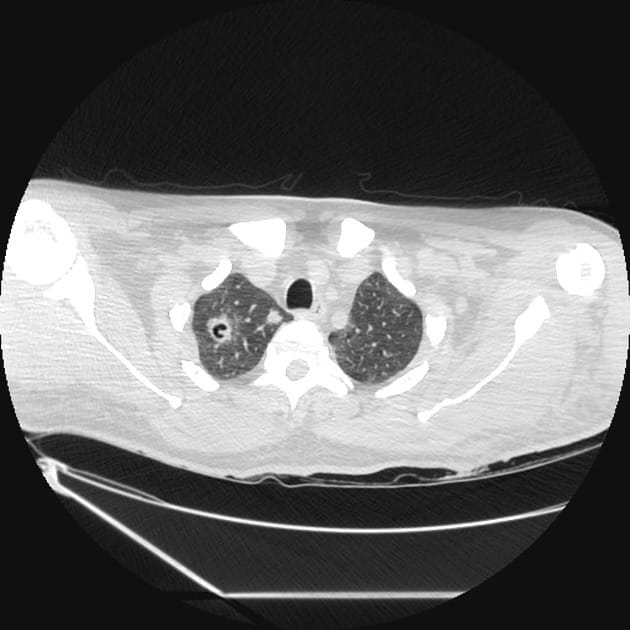

Kryptokokoza płucna

Postać płucna może przebiegać bezobjawowo lub manifestować się przewlekłym kaszlem, odksztuszaniem dużych ilości wydzieliny, dusznością i bólem opłucnowym, a nawet niewydolnością oddechową. Zakażenia objawowe zazwyczaj rozwijają się powoli, w ciągu tygodni, a w przypadku immunosupresji – w ciągu dni. W badaniach obrazowych stwierdza się guzki, nacieki lub zmiany jamiste, niekiedy imitujące gruźlicę lub nowotwór [3]. Rozpoznanie kryptokokozy płucnej zawsze wymaga wykluczenia zajęcia OUN.

Identyfikacja czynnika etiologicznego polega na wykonaniu preparatu bezpośredniego, hodowli na odpowiednich pożywkach, badaniach serologicznych, histologicznych oraz molekularnych [1–3]. Warto wykonać badania obrazowe głowy i klatki piersiowej w celu oceny rozległości choroby i obecności guzków.